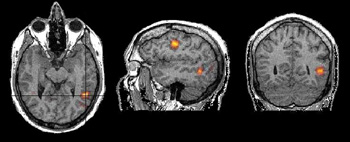

Functional magnetic resonance imaging (fMRI) is a development of MRI techniques that allows visualization of brain functions related to specific tasks. The study does not require any substance to be administered since it is based on the indigenous brain vascular response, requiring only cooperation for periods ranging from 15 to 60 minutes.

To date, several tasks have been utilized for mapping the brain cortex. Simple tasks include stimuli based on presentation of light, colors, tones, chords, music, syllables, movement of fingers and basic sensory perceptions. More complex and refined experiments have been implemented to map subtle cognitive functions. Currently, there is a vast armamentarium for mapping memory, attention, inhibition, face recognition, sensory discrimination, fear, etc.

However, most fMRI work has been directed in mapping language. Language mapping has been performed in children and adults. Reading, listening to meaningful text, generating words, making semantic decisions, are the most frequent paradigms described in the abundant current literature on fMRI. The technique has received ample acceptance among neuroscientists interested in epilepsy for the potential it has to become a tool to replace the Wada test.

Functional MRI is based on small signal changes that result from the following cascade of events. A task elicits activation in one or several brain areas. These areas increase their metabolic demands, suffer vasodilatation, and alter their levels of deoxyhemoglobin and oxyhemoglobin. Since deoxyhemoglobin is a paramagnetic molecule, it influences the phase of local proton-spins, altering the source signal that is converted into images. Therefore, the image is a representation of local changes of levels of deoxyhemoglobin, related to the brain region performing a task.